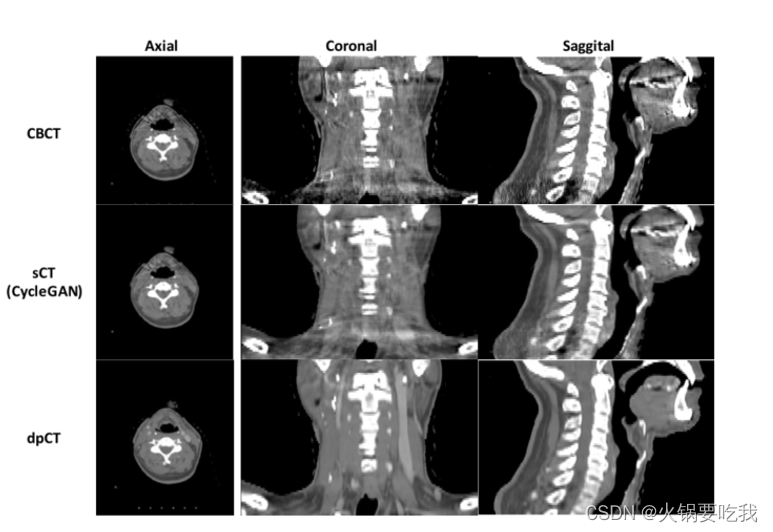

实验结果: